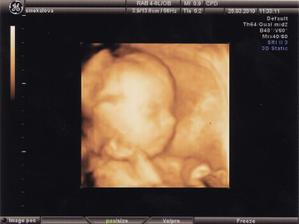

25.3.2010 - poslední UZ na genetice, opět nám potvrdili, že je vše v pořádku a udělali nám 3D snímek naší (teď už) Natálky